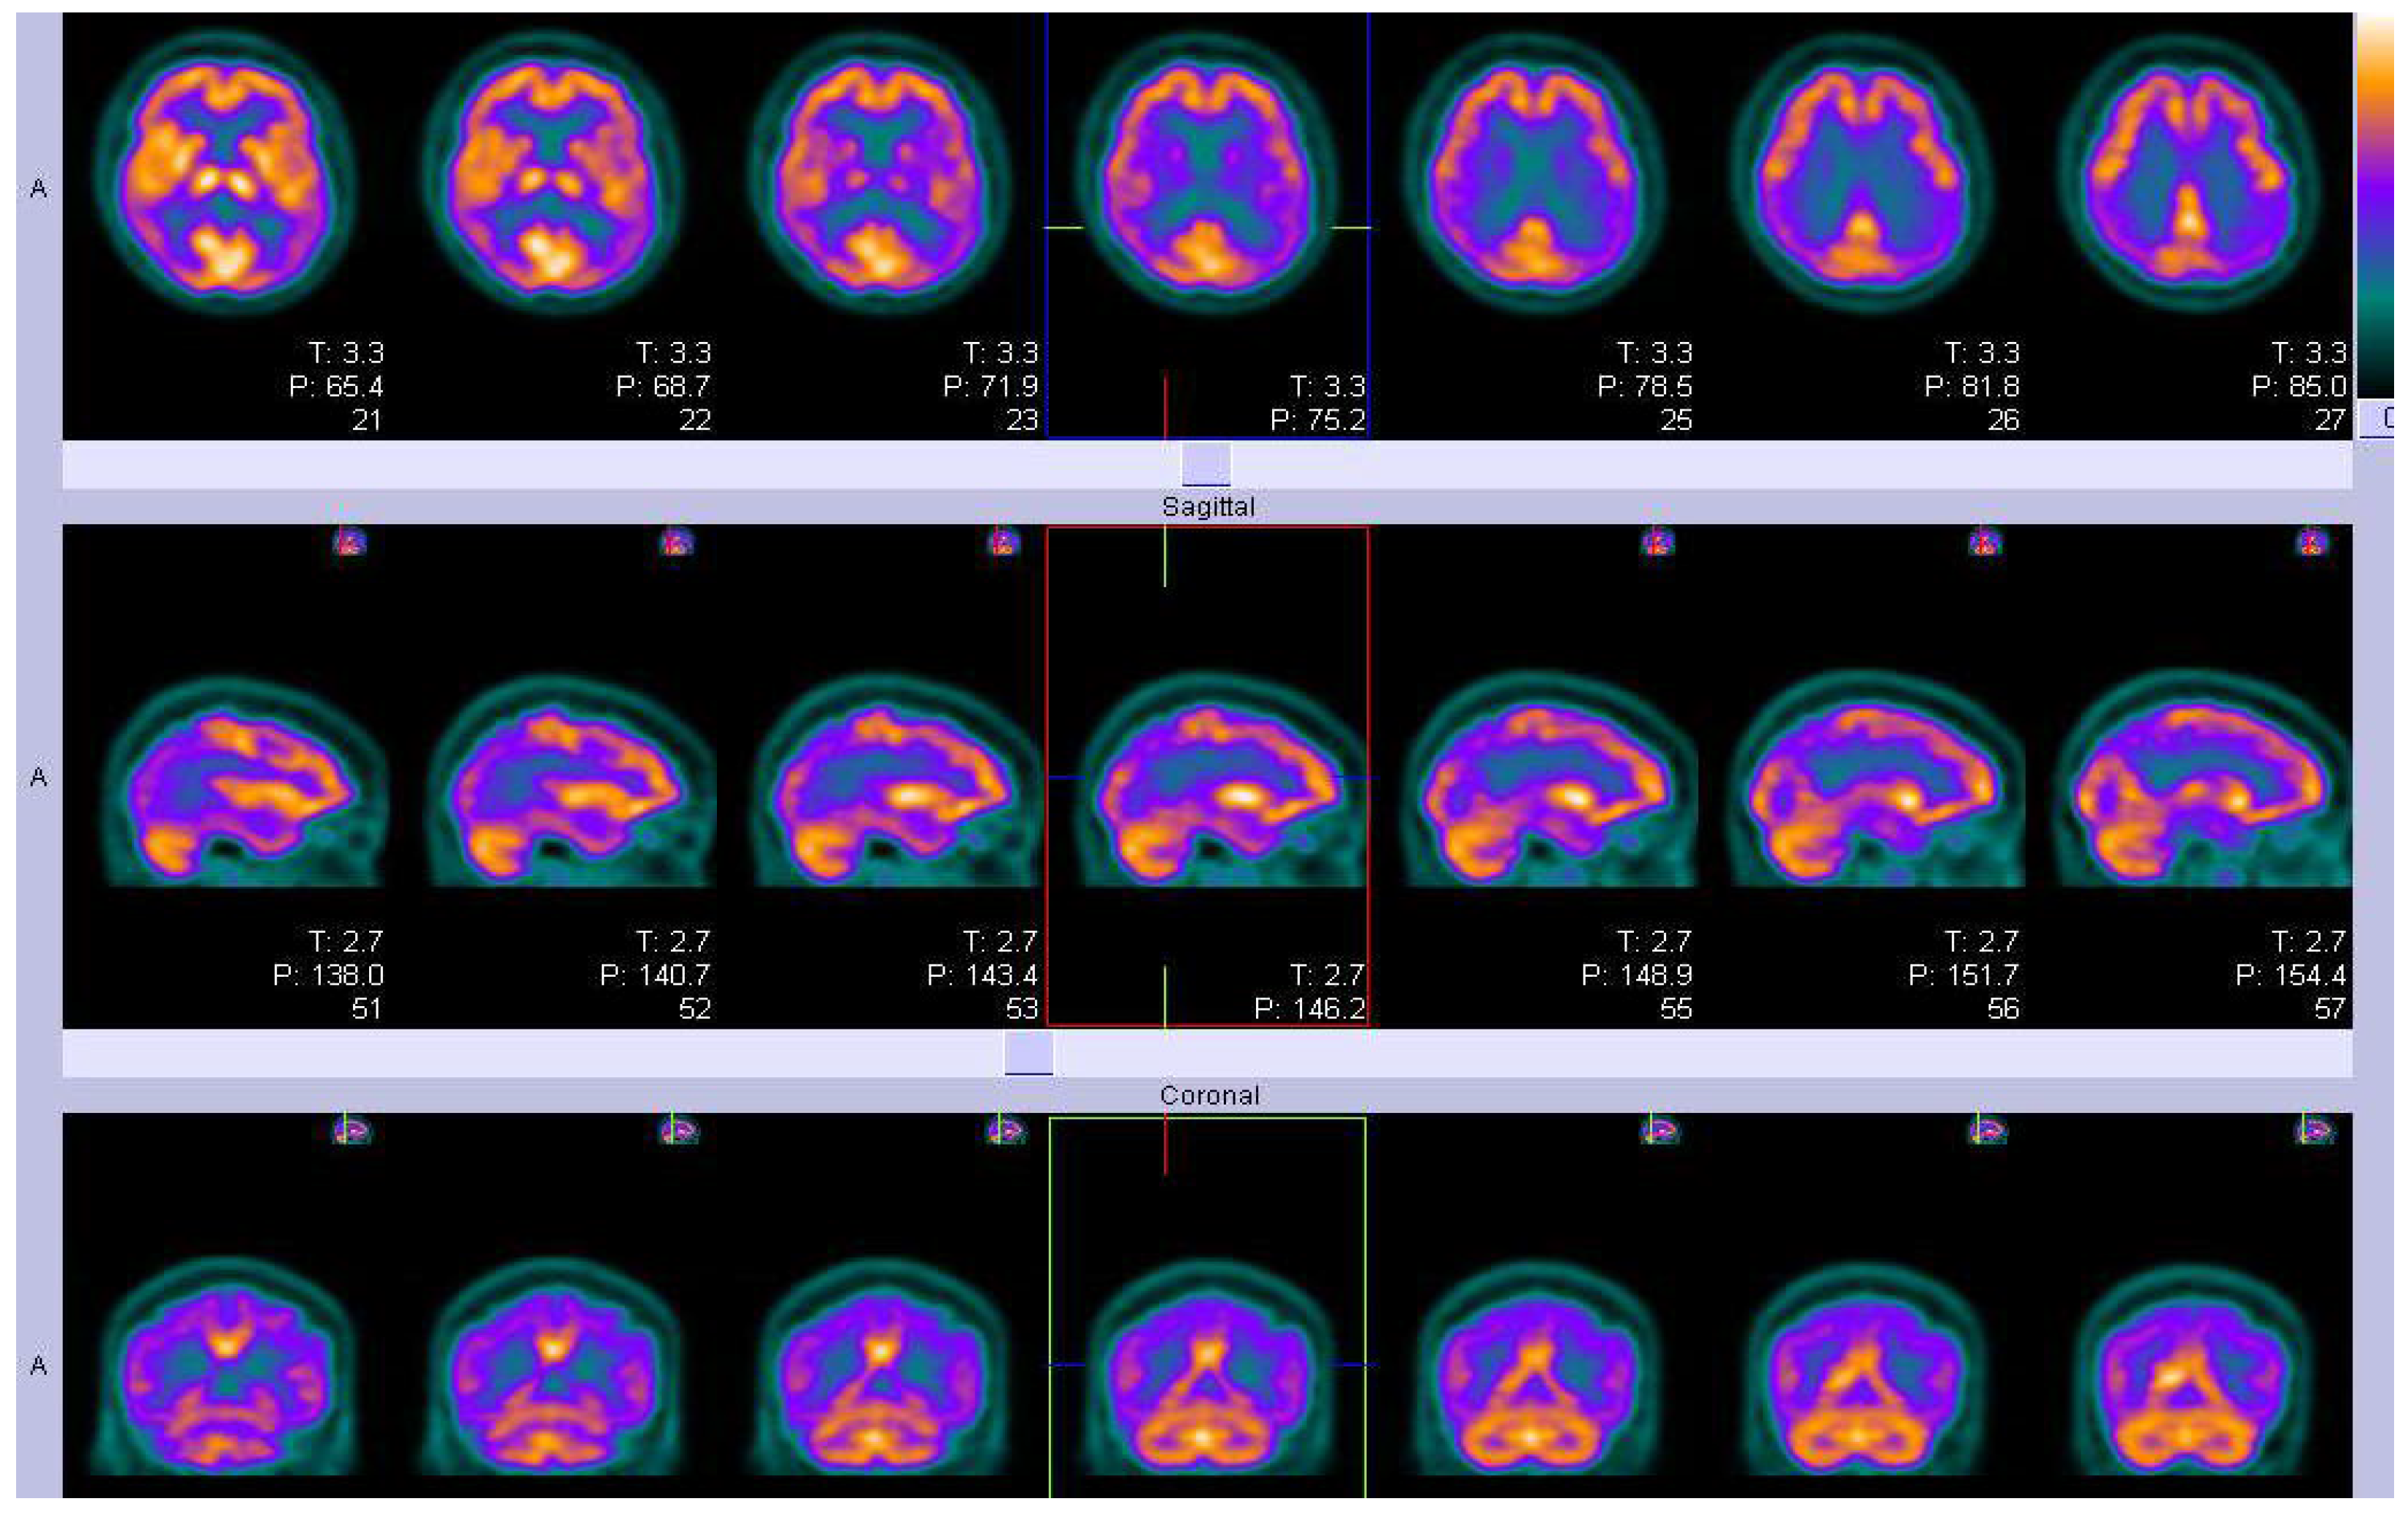

Figure 5.

Parametric 18 F-AV-1451 images across stages. In general, 18 F-AV-1451 SUVr increased throughout the cortex and subcortex from stage 0 to stage 4. Participants in stage 0 had tau levels corresponding to those of normal young adults. A dominating tau elevation in medial temporal regions (Braak I/II ROIs) was shown in stage 1. While stage 2 presented increased SUVrs in extramedial temporal regions, stage 3 showed greater SUVrs increase in Braak III/IV ROIs, including the inferior and lateral temporal lobes. Stage 4 had significantly elevated 18F-AV-1451 SUVr extending into the neocortex. ROI, region of interest; SUVr, standard uptake value ratio. Reproduced with permission [118].